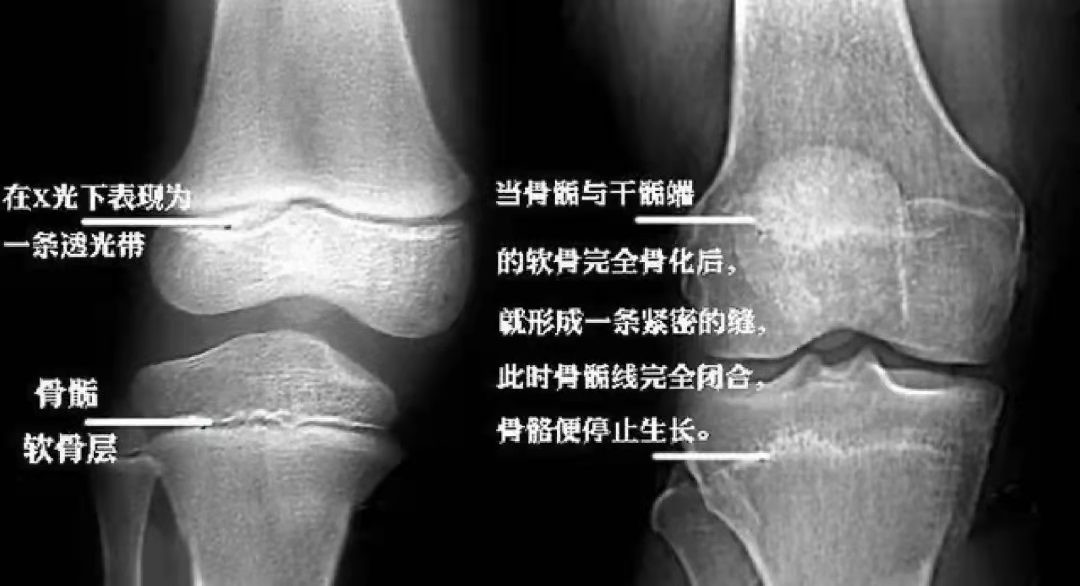

骨骺与干骺端之间的软骨,在x光片上表现为一条较宽的透光带,这条透光

骨骺与骨干之间有一层软骨层,医学上称之为骺软骨 ( 骨骺线).

的不断释放,骨头生长的通道被「封死」,最后形成传说中的「骨骺线」